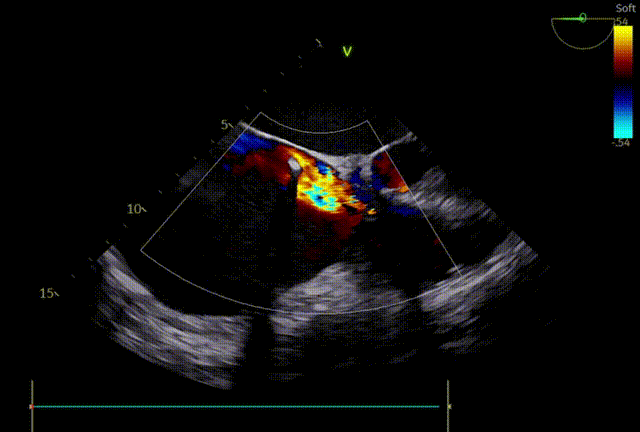

术前超声

术后超声